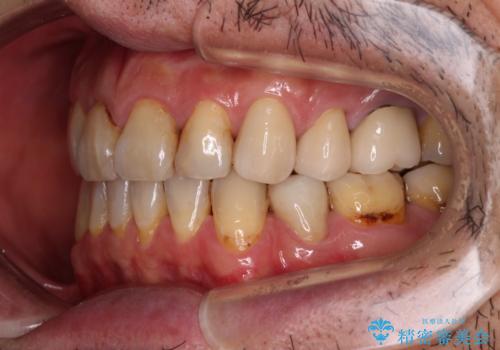

- むし歯による奥歯の痛みを気にして来院された患者様です。

神経にまでむし歯の及んでいる歯や、既に根管治療がされている歯に痛みがあったため、まずは根管治療を行うこととしました。

その後、以前行った抜歯矯正の後戻りをインビザライン・ライトにより改善し、むし歯や銀歯はオールセラミッククラウンにて補綴治療することとしました。

痛みは速やかに引き、銀歯や黒く変色したむし歯がセラミッククラウンで自然な色合いに仕上がり、患者様には大変満足していただきました。